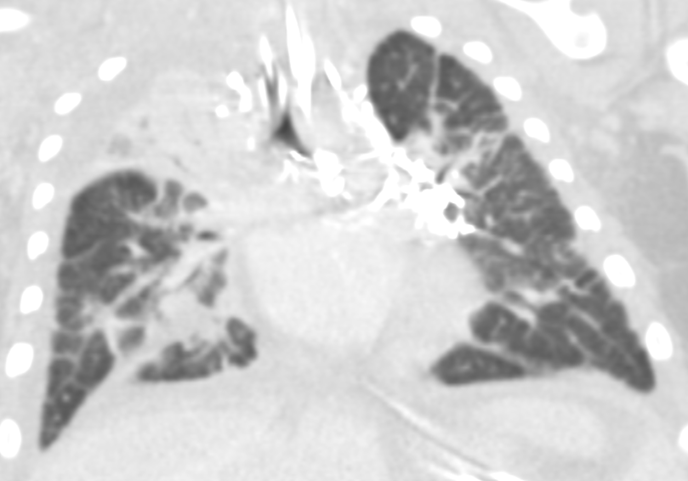

Chest radiographic findings include prominent interstitial markings, hyperinflation, ground-glass opacities especially in neonates, and pleural effusion. Chest CT may show diffuse or segmental interlobular septal thickening, perihilar infiltrates, ground-glass opacities, and hyperinflation (Fig 3). Pleural fluid analysis is consistent with chylous pleural effusion. Diagnostic criteria include a milky or opalescent appearance of the pleural fluid, elevated triglyceride levels(typically >110mg/dl), and lymphocyte predominance on cell count. In neonates and young infants who may not yet be enterally fed, triglyceride levels may be lower, therefore diagnosis may rely on lymphocyte predominance(>80%) and increase in triglyceride content following initiation of enteral feeds. These findings support impaired lymphatic drainage, as seen in congenital pulmonary lymphangiectasis. Lung biopsy with histology and immunochemical staining demonstrating dilated lymphatic channels and thickening of the interlobular septa and subpleural space is the gold standard for diagnosis. Immunohistochemical staining for endothelial cell markers CD31, CD34, and D2-40 confirms lymphatic origin. Echocardiogram should be performed to rule out pulmonary venous obstruction, such as hypoplastic left heart syndrome or TAPVR, which can cause secondary lymphangiectasia. Lymphangiograms have been used in some patients to evaluate thoracic duct disruption and lymphatic duct dilation. In our patient Echocardiogram showed large left pleural effusion, PFO with bidirectional flow, mild bilateral pulmonary artery stenoses, and normal biventricular systolic function.